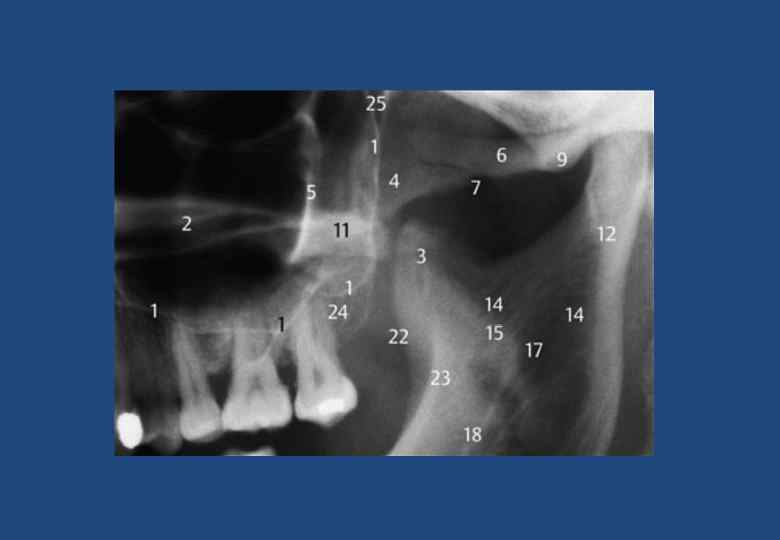

• • • • • • • 1. Верхнечелюстная пазуха границы 2. Горизонтальная пластинка небной кости и латеробазальная граница полости носа 3. Венечный отросток, наслаивающейся на крыловидный отросток клиновидной кости, бугор верхней челюсти и мягкие ткани небной занавески 4. Тело скуловой кости с безымянной линией 5. Безымянная линия (линия на височной поверхности скуловой кости) 6. Скуловая дуга 7. Височно-скуловой шов 8. Суставная ямка 9. Суставной бугорок 10. Мягкие ткани ушной раковины 11. Наружный слуховой проход 12. Мыщелковый отросток и головка нижней челюсти 13. Шиловидный отросток височной кости 14. Верхние отделы глотки 15. Небная занавеска 16. Спинка языка 17. Отверстие нижнечелюстного канала 18. Нижнечелюстной канал 19. Передний бугорок первого шейного позвонка 20. Зуб второго шейного позвонка 21. Отверстие поперечного отростка второго шейного позвонка 22. Наружная косая линия (продолжение переднего края в каудальном и боковом направлениях) 23. Височный гребень 24. Бугор верхней челюсти 25. Крыловидно-небная ямка